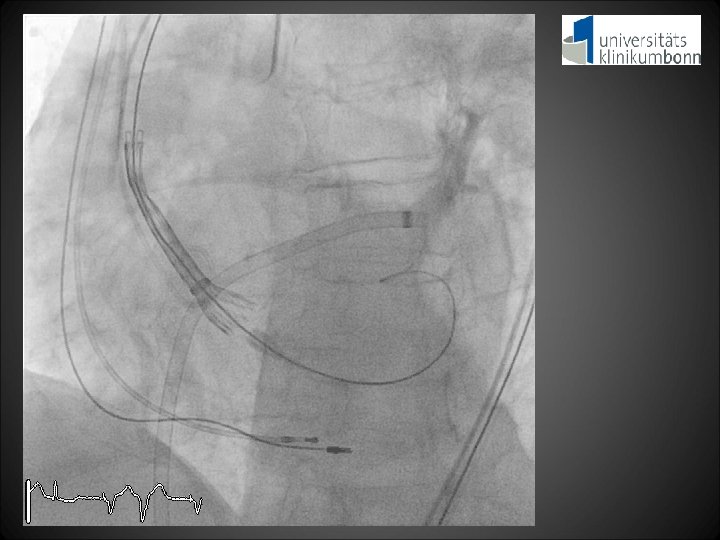

Screening Imaging Studies Heart catheterization: 2 -vessel-CAD with patent stents in LMS, RCX and D 1 CT scan: Aortic annulus 27. 9 x 23. 5 mm 2, perimeter 81 mm Sufficient diameter of aortoiliac vessels for transfemoral access Echo: Severe aortic stenosis, AVA 0. 9 cm 2, annulus 28 mm, AR 2, MR 1 Procedural Strategy Transfemoral TAVI (31 mm prosthesis) with cerebral protection device Clinical Indication 1. Severe aortic stenosis with comorbidities 2. High surgical risk (STS score 9. 3%, log. Euro. SCORE 37. 4%)

RRsys 110 mm. Hg RRdia 37 mm. Hg LVEDP 7 mm. Hg Aortic regurgitation Index = [(RRdia – LVEDP) / RRsys] x 100 = [(35 - 7) / 110] x 100 = 25. 5